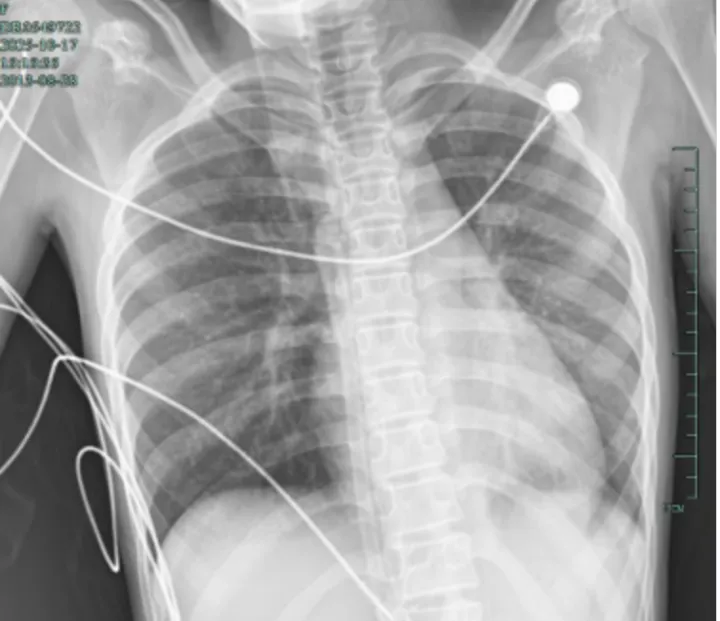

治疗后,“白肺”被吸收,心脏边缘清晰可见

值得高兴的是,笑笑的“白肺”基本吸收,恢复如常,没有留下严重的并发症。